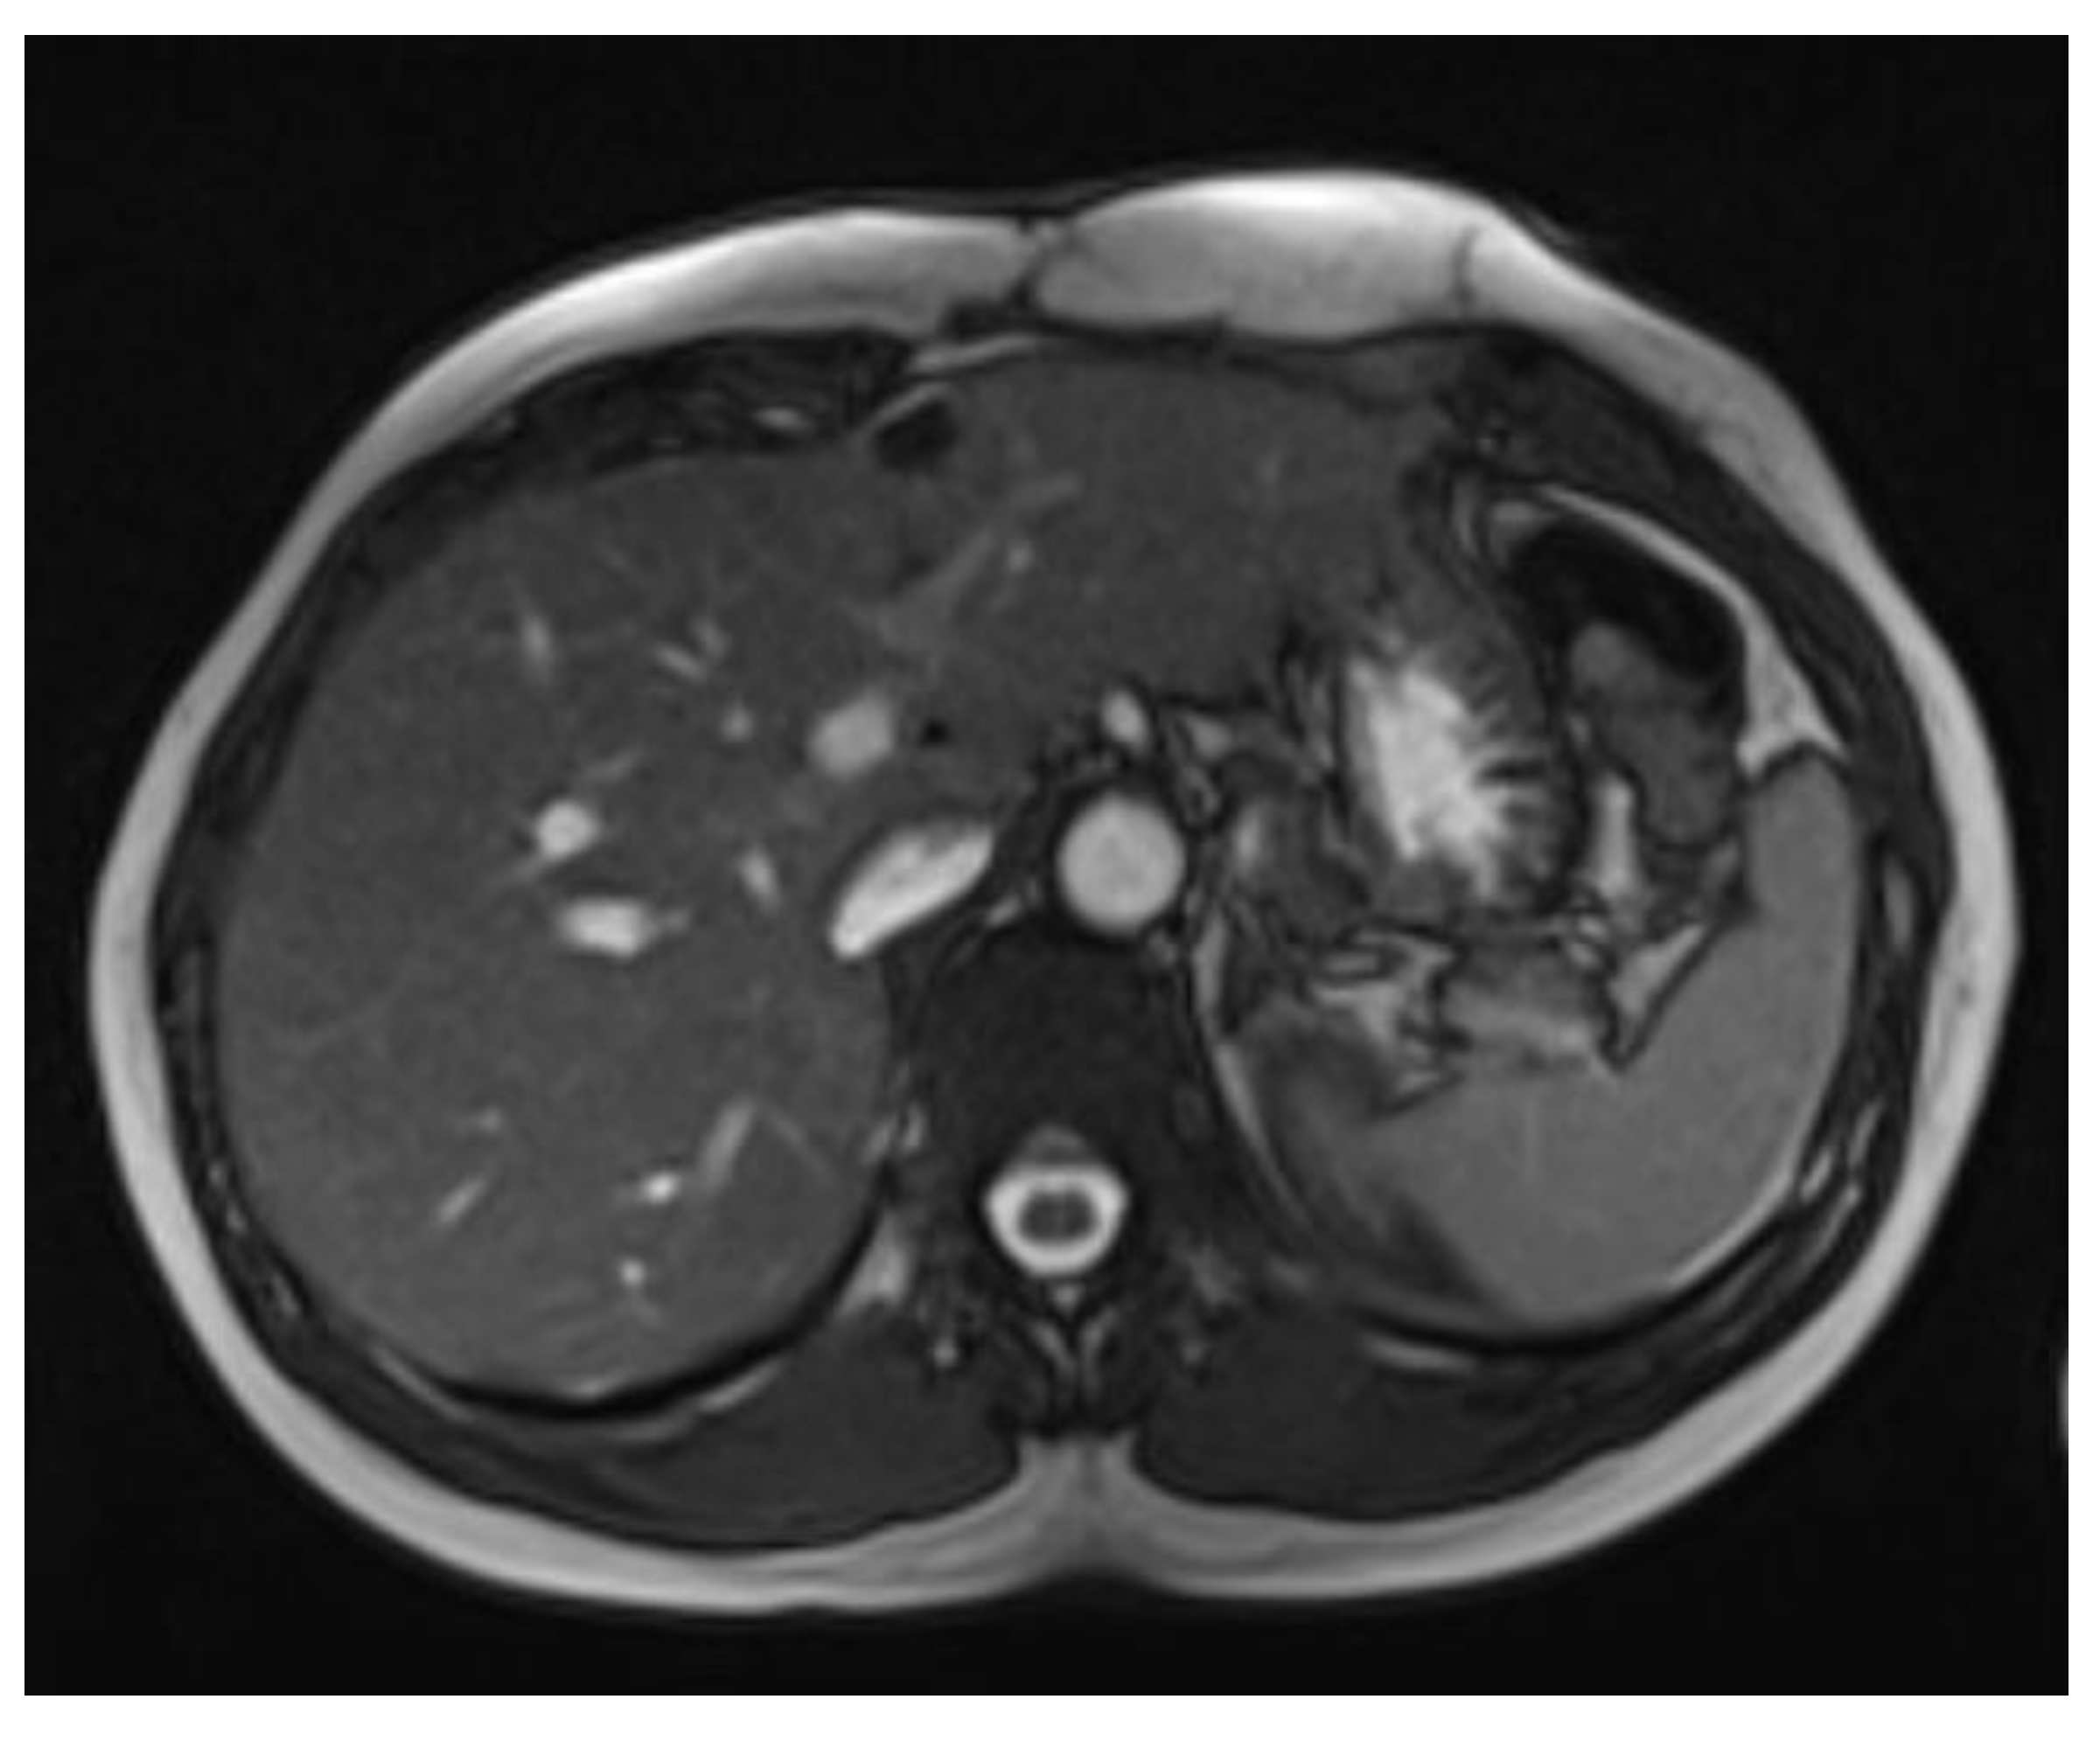

By May 2022, MRI imaging revealed tumor recurrence (28 × 50 × 84 mm, AP/LL/CC). Due to the progressive nature of the recurrence, an oncological evaluation was recommended. The patient sought further assessment at the Fondazione IRCCS Istituto Nazionale dei Tumori in Italy, where the recurrence was confirmed, with a maximum tumor diameter of 8 cm. (Figure 4 and Figure 5). The medical team advised against further surgery and recommended conservative management, including chemotherapy with methotrexate, vinorelbine, VEGF inhibitors, and anthracyclines. However, the patient declined chemotherapy and opted for systemic treatment.

Figure 4. MRI imaging of desmoid tumor with intrathoracic localization.

Figure 5. MRI imaging of desmoid tumor with intrathoracic localization.